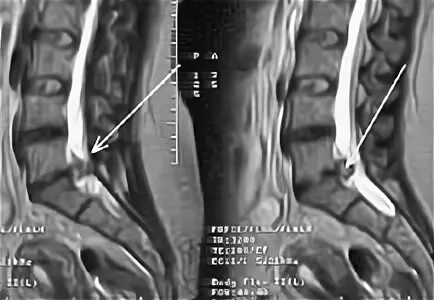

L5 s1 как лечить